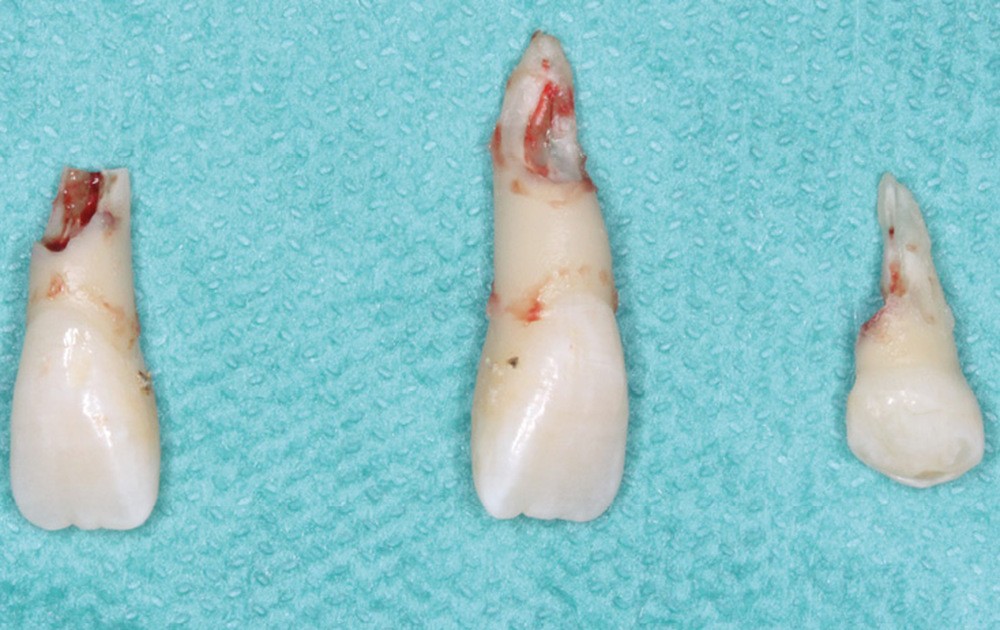

Le plan de traitement choisi comprend les extractions de 63, 12, 22, 34 et 44. Ce choix s’est porté d’une part sur le fait de la présence de résorptions très avancées de 12 et 22 et d’autre part sur la correction de la biproalvéolie facilitée par l’extraction de 34 et 44 qui ont par ailleurs un diamètre légèrement inférieur à 35 et 45.

Les extractions de 12, 22, 63, 34 et 44 ont été réalisées dans un premier temps. Un cache esthétique en résine composite a été élaboré à partir d’une clé en silicone obtenue sur les empreintes initiales et collé sur 11 et 21 afin de limiter l’impact psychologique de telles extractions (fig. 2a-b).